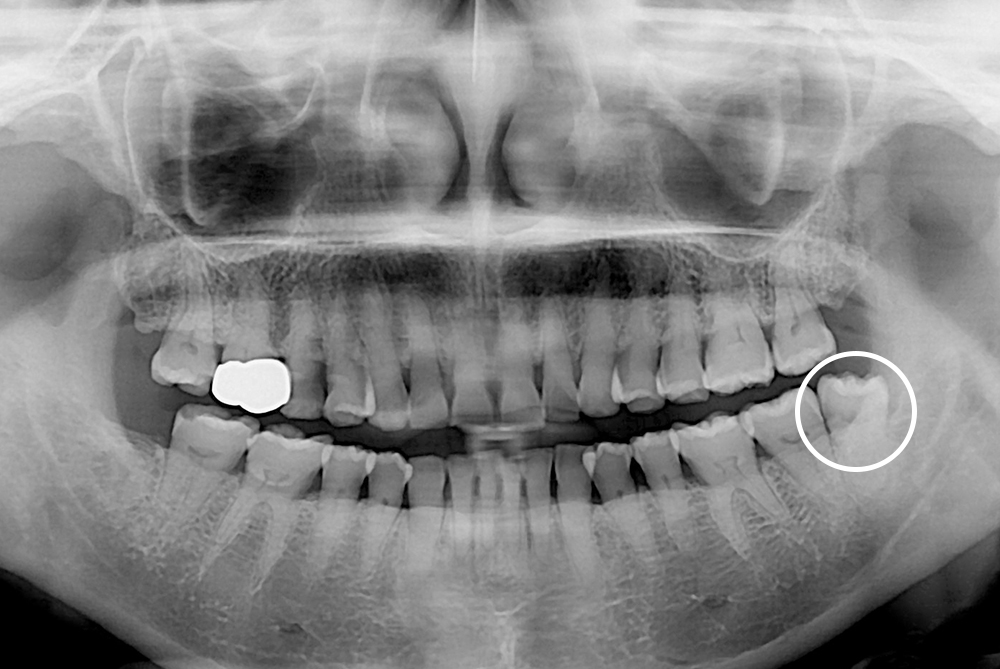

[사랑니] 매복 사랑니 발치

치료후 : 2020-05-28

세종치과는 구강악안면외과학 박사이신 원장님이 발치하는 치과입니다.